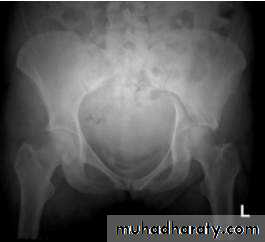

Radiological examination

two questions must be answered.

Is there a fracture?

Is it displaced ?

:Radiological classification

GRADE 1

:the femoral head is in its normal position or tilted into valgus and impacted on the femoral stump.

GRADE 2

The femoral head is normally placed and the fracture line may be difficult to diagnosed

GRADE 3

The femoral head tilted out of position and the trabecular marking are not in line with those of innominate bone.

GRADE 4

The femoral head trabeculae are normally aligned with those of innominate bone.